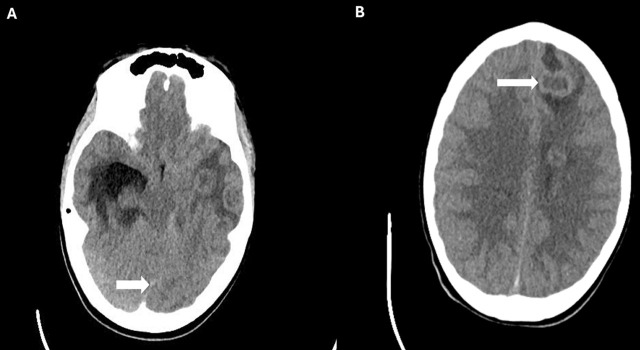

Case presentation: A 12-year-old adolescent male who had headache and photophobia and was diagnosed with multiple brain abscesses and was refractory to conventional medical and neurosurgical intervention. A single dose of 10 mg vancomycin was administered through endo-ventricular drain, resulting in resolution of abscesses and alleviation of symptoms.

Conclusion: We describe the first instance of intraventricular vancomycin use in the pediatric age group for the treatment of multiple brain abscesses. Given the variability in dosing reported in the literature, our case report warrants further studies to standardize dosage for this rare intervention.